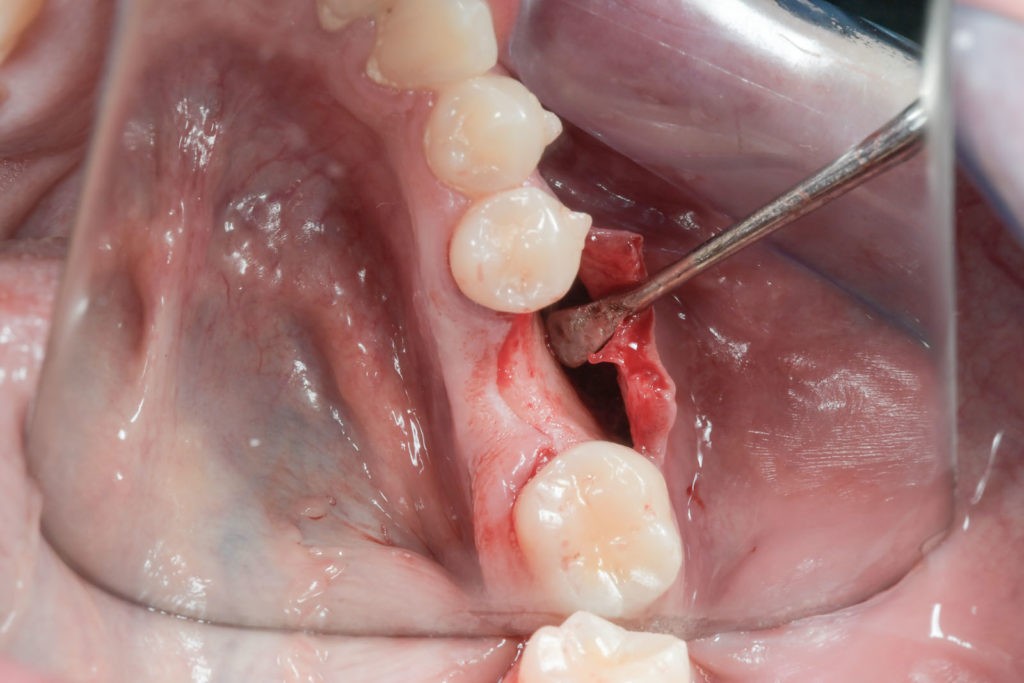

• Użycie drobin kości własnej do pokrycia ubytków na niewielkim obszarze, jak obnażenia gwintu implantu podczas implantacji, obnażenie korzeni zęba czy furkacji korzeniowych. Wiórki kostne pobierane są podczas zabiegu specjalnymi aplikatorami (skrobaczkami) z powierzchni kości szczęk i żuchwy.

• Bloczki kostne pobierane podczas zabiegu regeneracyjnego z okolicy jamy ustnej z kości żuchwy lub szczęki dla rekonstrukcji mniejszych trójwymiarowych ubytków kostnych.